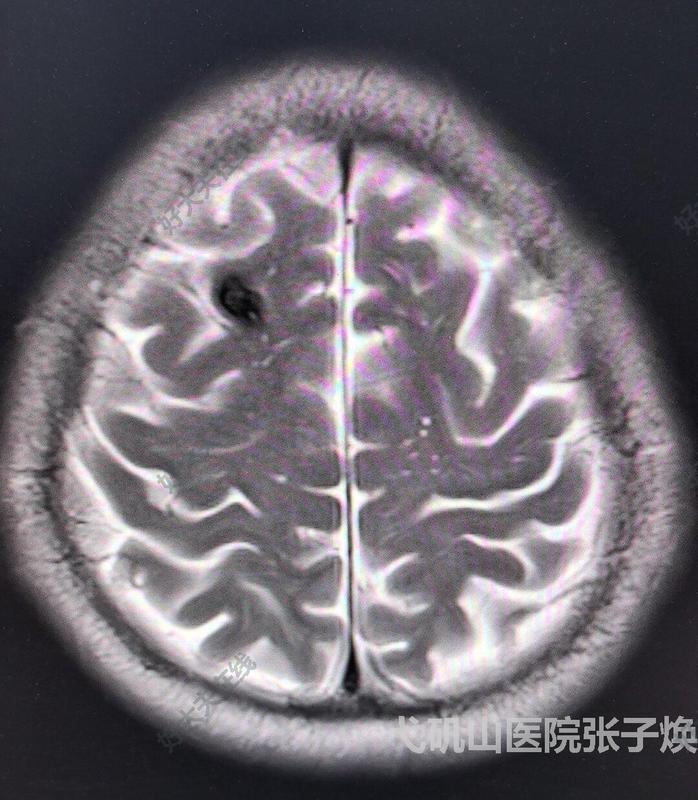

治疗前症状性右额上回海绵状血管畸形,可以采用额瓣,定位、手术难度不大。治疗中正好我们复合手术室,利用DSA更加精准定位,5cm直切口小骨瓣。治疗后治疗后7天皮内缝合,不用拆线。治疗后即刻病变完全切除,创面小,无出血。

张子焕医生的科普号